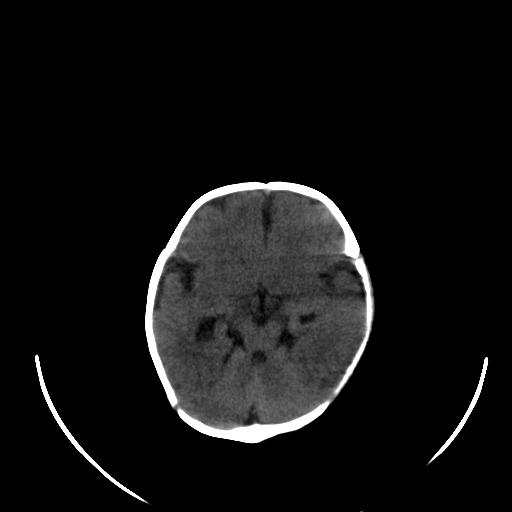

患儿 女性 1个月  今天发现阵发性抽搐  双眼上翻、凝视,嘴唇及面色青紫

考虑双侧脉络膜裂囊肿。

双侧颞枕叶片状低密度影,考虑新生儿却血缺氧性脑病可能

左侧额叶见班片样低密度灶,症状像癫痫,可能与之有关。

新生儿却血缺氧性脑病不排除!

左侧额叶见班片样低密度灶,建议mr

考虑hie。

考虑新生儿hie。